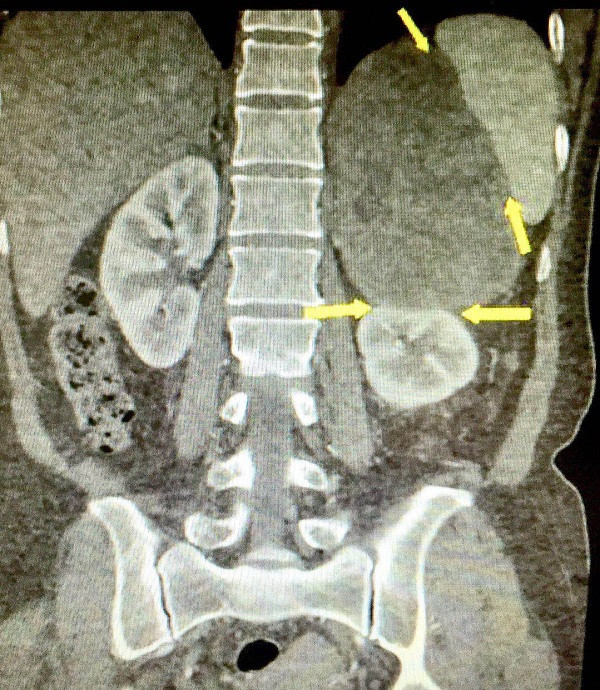

影像“臟器重建”,精準(zhǔn)定位腫瘤位置。潘女士介紹,一年多前,她總是覺得頭暈、頭痛、渾身不適,血壓的上壓經(jīng)??梢赃_(dá)到200mmHg,心悸難受時多次呼叫120急救。經(jīng)過全面檢查,她被診斷為“腎上腺嗜鉻細(xì)胞瘤”,若不及時治療,隨時危及生命。

因腫瘤體積較大,且與腹主動脈、脾血管、左腎血管粘連,切除腫瘤的手術(shù)風(fēng)險過大,不少醫(yī)院拒絕收治。這顆“心腹大患”令潘女士一家人都“心驚驚”,她輾轉(zhuǎn)求醫(yī)到廣州市第一人民醫(yī)院。

“手術(shù)切除嗜鉻細(xì)胞瘤是最有效的治療方法,但像潘女士這樣的情況,腫瘤與腹主動脈等多臟器血管粘連,手術(shù)風(fēng)險極高?!标悩I(yè)輝介紹,為了提高準(zhǔn)確性,術(shù)前,影像科的醫(yī)生通過“臟器重建”,將重要的部位突出顯示,精準(zhǔn)定位腫瘤的位置、血液供應(yīng)情況及腫瘤與周圍臟器的關(guān)系。